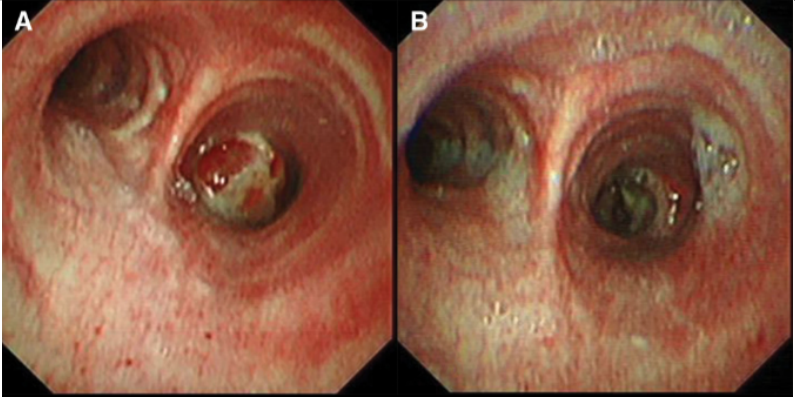

支气管镜在肺真菌病治疗中的应用主要有:①通畅气道:清除气道潴留物,解除机械阻塞。②冲洗引流:脓腔冲洗引流;液性病灶穿刺引流;炎症部位支气管冲洗;导管冲洗;穿刺引流。③局部用药:支气管冲洗、留置导管注药、药物缓释系统置入。病例:一名45岁男性因咳嗽、咳黄痰、呼吸困难持续5个月入院,患者胸部CT提示肿块引起的阻塞性肺不张(图3),但初步病理活检并未明确支持肿瘤诊断。这种不确定性可能与浅表取样有关,但不能完全排除肿瘤病变,使用硬质支气管镜检查缓解气道阻塞。术中见气道内白色肿块,该肿块松散地附着在支气管壁上(图4),镊子取出肿块时出血极少。肿块的组织学检查显示慢性化脓性炎症和肉芽肿形成、提示新型隐球菌感染。通过宏基因组二代测序证实了BALF中新生梭菌的存在。同时,血清隐球菌荚膜抗原检测结果呈阳性,氟康唑抗感染后痊愈。注:A:右主支气管和右中支气管有肿块,右下叶不张;B:右主支气管肿块消失,肺复张;C:右主支气管肿块完全消失和完全肺复张。图源:Medicine (Baltimore), 2024, 103(12):e37455.注:A:硬质支气管镜检查前软性支气管镜检查,显示右侧主支气管有肿块,导致闭塞;B:硬质支气管镜检查3天后软性支气管镜检查,证明成功从右侧主支气管中切除肿块。图源:Medicine (Baltimore), 2024, 103(12):e37455.隐球菌病胸部CT大部分表现为结节影,部分可有实变和坏死。支气管内隐球菌病导致的严重气道阻塞病例罕见,我们认为选择早期呼吸干预是一种理性的选择。首先,近一半的阻塞性支气管内隐球菌病患者对抗真菌药物反应不佳。其次,长期肺不张对肺复张构成挑战,可能导致永久性肺塌陷和肺功能受损,甚至最终导致肺实质感染和纤维化。软性支气管镜检查有助于区分内在性梗阻和外在压迫性,而硬质支气管镜检查可以更好地了解内在性梗阻性病变的性质,并提供一种气管内治疗手段。毛霉菌极易堵塞局部血管和支气管,病灶药物浓度低,单纯的全身药物治疗效果并不理想。近年来的研究发现两性霉素B局部给药,在抗真菌治疗方面会起到一定的辅助作用,包括雾化吸入、鞘内注射等,经支气管镜应用两性霉素B局部灌注对肺毛霉病可取得良好的效果。对于支气管被毛霉的菌丝体阻塞的患者,采用积极的介入治疗也可取得一定的效果,但应小心谨慎,防止出现大出血。各种介入治疗方法,包括两性霉素B局部灌注、冷冻治疗等,获得了不错的疗效。肺毛霉病的介入治疗必须具备全身麻醉、气管插管、预置球囊及有经验的呼吸内镜介入团队等。冷冻治疗建议在全麻气管插管方式下实施,出血风险高的患者还需要预置止血球囊。研究报道,10例肺毛霉病介入治疗患者均临床治愈,死亡0例。10例患者中应用冷冻探头冻取病灶8例,活检钳钳除病灶7例,套器套治疗2例,异物钳钳取病灶2例。介入和治疗经支气管镜直接局部灌注同步进行,1次/周,共1~6次。冷冻治疗的过程中3例患者预置球囊防止支气管内出血。10例患者中4级出血1例,3级出血2例,2级出血4例,3例患者无出血。支气管内出血均在5~10 min停止,术后少量痰中带血3~4天,术后气胸0例。牟向东教授团队在应用全身+局部治疗肺毛霉病的同时联合气管镜下介入技术清除阻塞气道和血管脓栓,并且在导航和超声定位下局部精准灌注两性霉素B,提高了肺组织内的药物浓度,降低了全身用药带来不良反应的概率,获得了显著的临床疗效,灌注后患者亦无明显不良反应(图5-图8)。注:右肺中叶和右肺下叶内基底段可见多发斑片影和片状肺内渗出实变影(箭头所示)。图源:https://www.btch.edu.cn/tszl/zbzx/fzjbzzzx/zb15blfx/91912.htm注:病理显示坏死组织内大量毛霉菌丝,并可见菌丝侵袭血管。